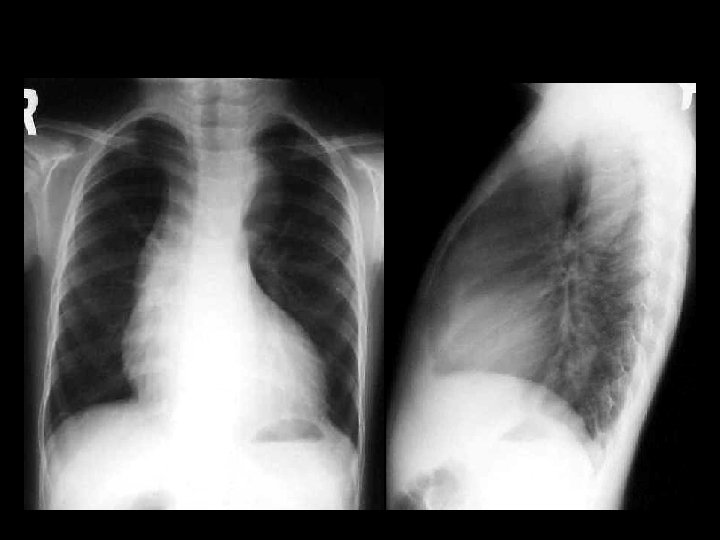

Tetralogy of Fallot • Findings: – elevation of the cardiac apex (RVH) – prominent right-sided arch, concave main PA – decreased pulmonary flow • Most common congenital cyanotic heart lesion • age of symptom onset related to degree of RV outflow obstruction • associated w/trisomy 21, TEF, and VACTERL